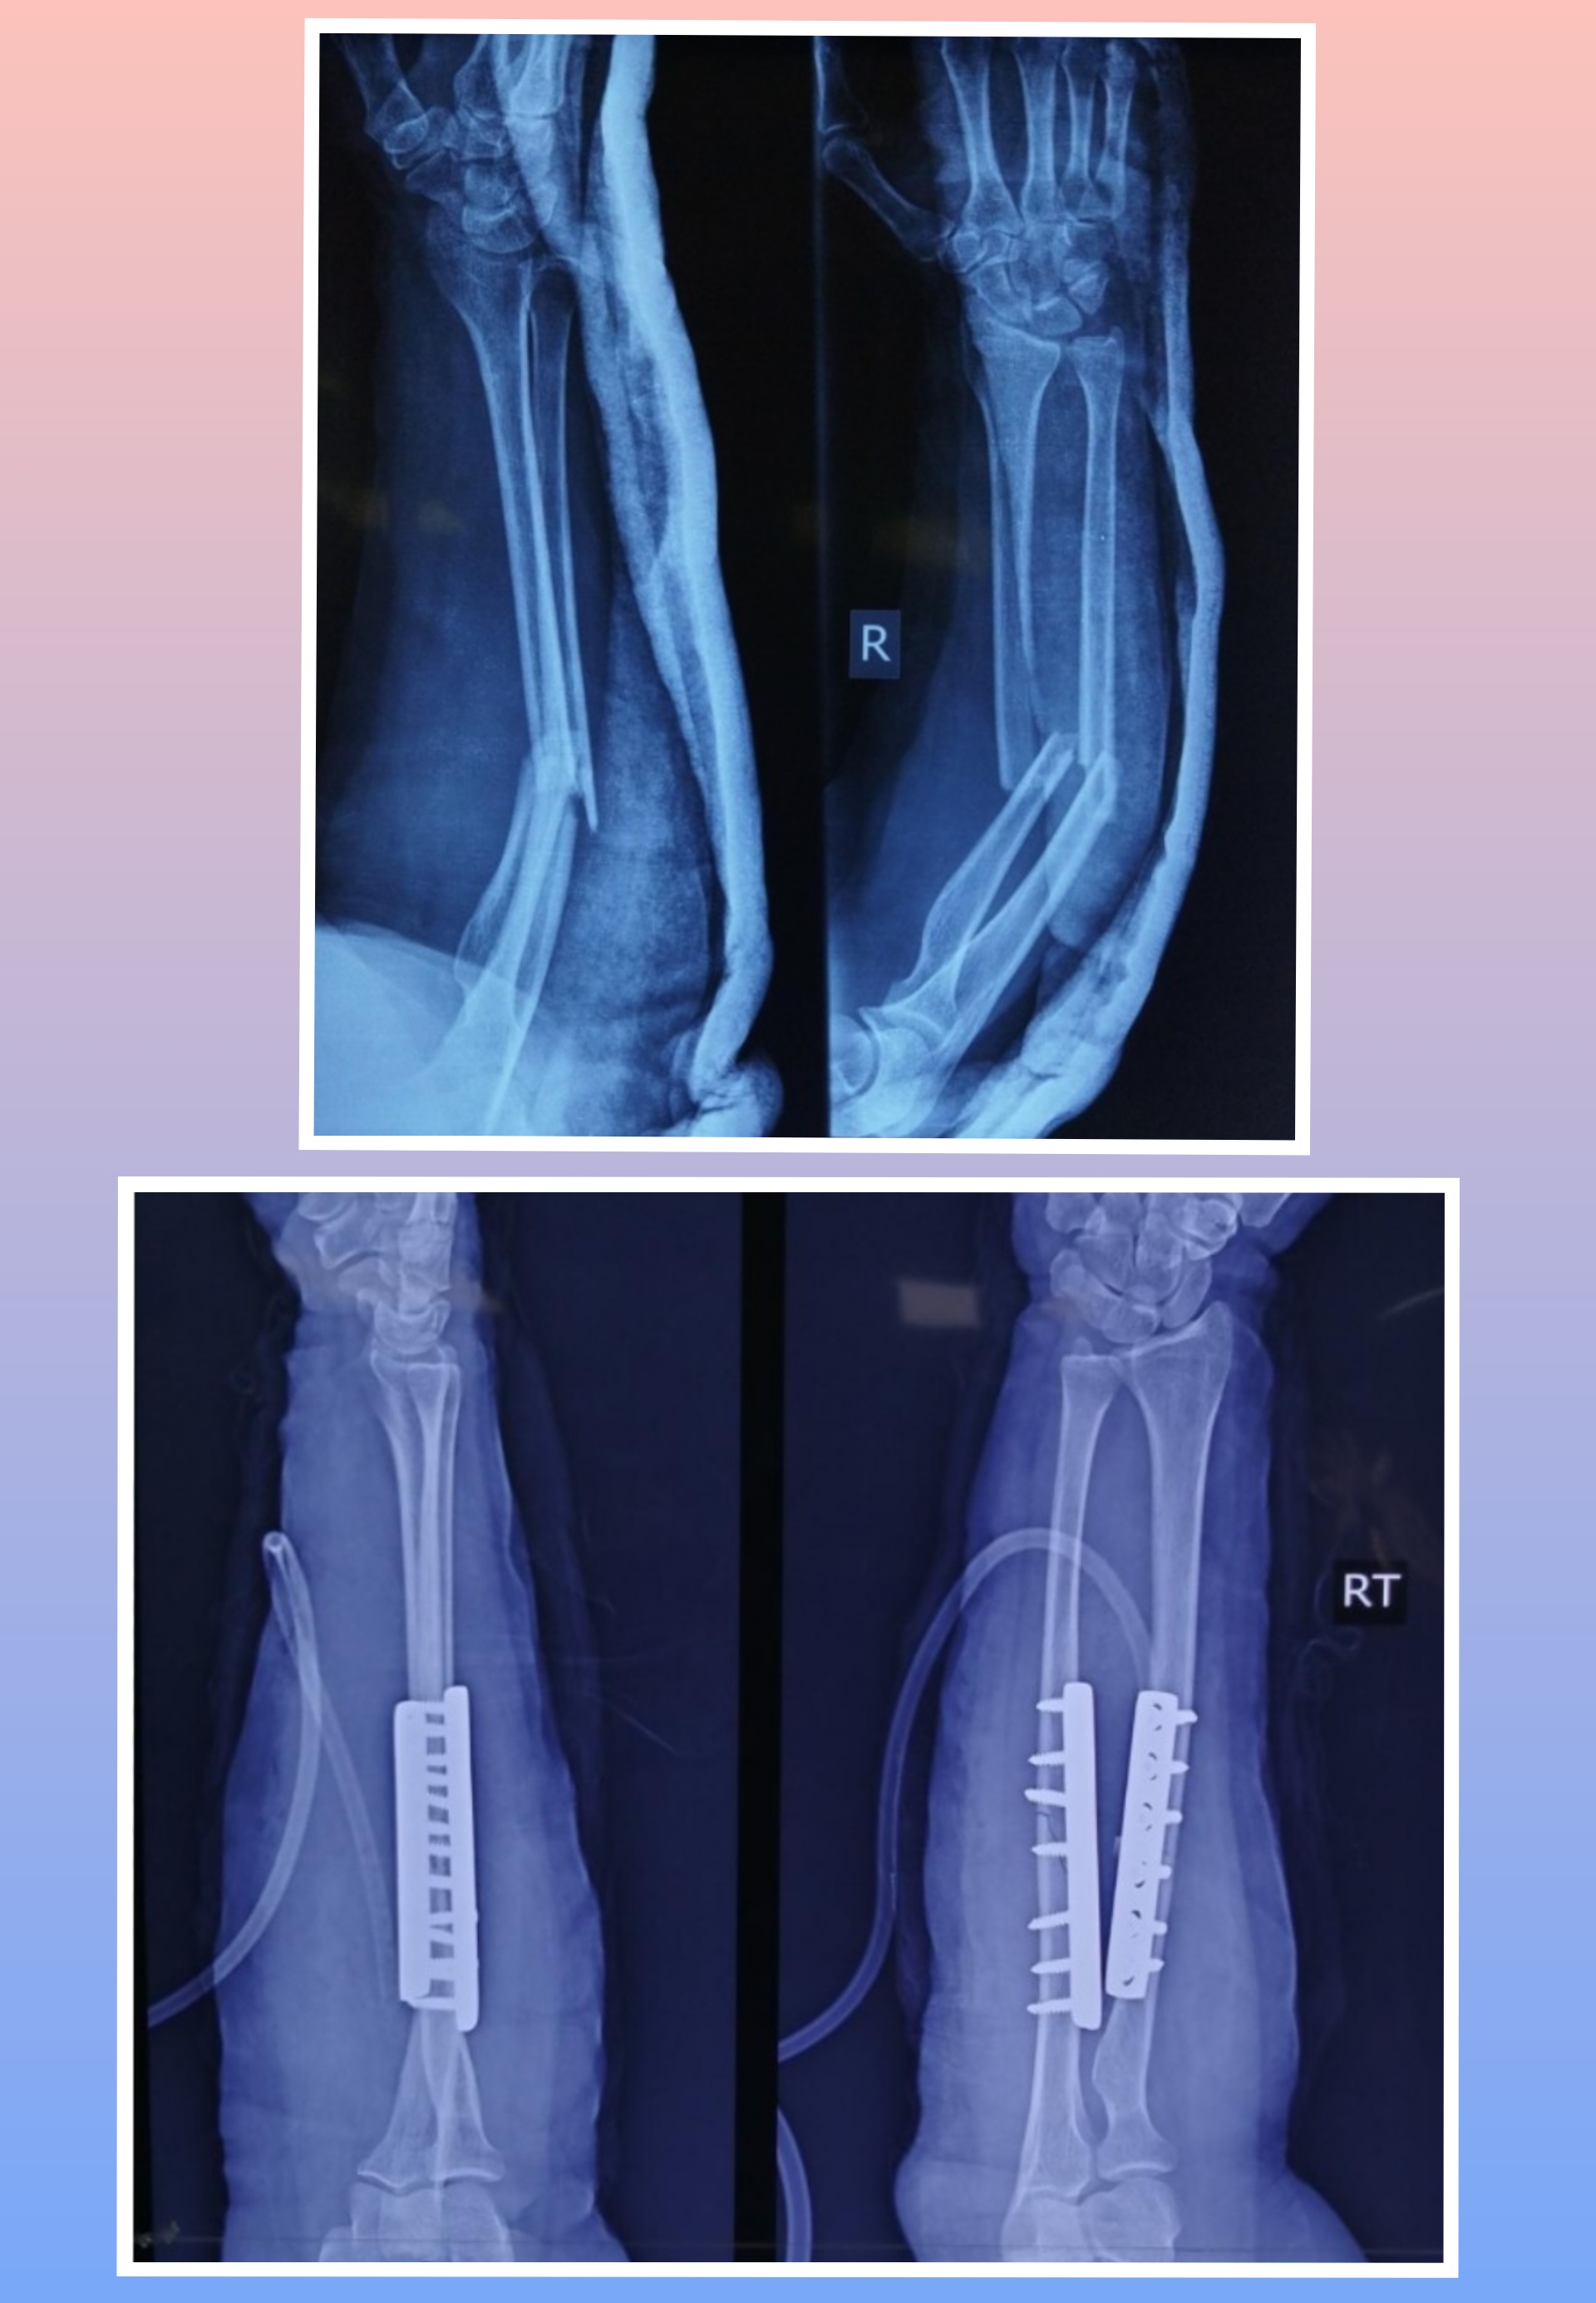

Warning: Graphic Content

The following section contains graphic images of surgical procedures. These images are intended for educational purposes and may be disturbing to some viewers. Viewer discretion is advised.

Surgeries